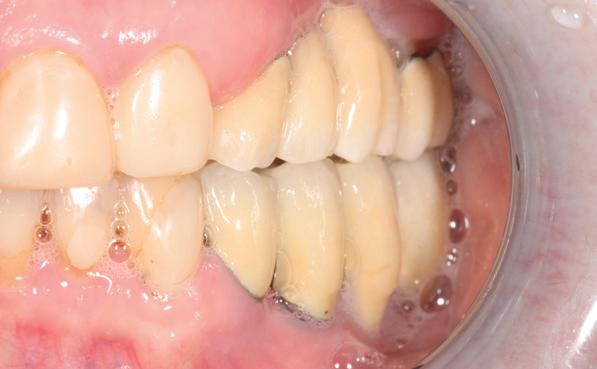

In de prothetische fase (zie foto’s) is in de bovenkaak gebruikgemaakt van verschroefde zirconia bruggen, die enkel buccaal zijn opgebakken. Deze bruggen zijn verlijmd op individuele, geanguleerde titanium abutments. In de onderkaak is een verschroefde kunststofbrug op een titaniumbasis (wrap-around) gemaakt. Voor deze combinatie is gekozen vanwege een minder hinderlijk tikkend geluid bij functie en kleinere kans op breuk van de keramiek. Een nadeel is verhoogde slijtage van de kunststof elementen, maar deze zijn in de jaren later eenvoudig te vervangen op de bestaande brug. Ondanks alle digitale mogelijkheden is de afdruk en registratiefase analoog uitgevoerd, omdat in ervaring van de behandelaren dit bij deze totale rehabilitaties op implantaten nog altijd de grootste precisie oplevert. Er is afgedrukt met impregum in individuele lepels en de pasvorm is gecontroleerd met rigide duralay bars. De relatie wordt vastgelegd zoals bij een volledige prothese met waswallen en pijlpuntregistratie. De opstelling in was wordt gepast en laatste correcties worden gemaakt in samenspraak met de patiënt, de restauratieve tandarts en de tandtechnicus. Na het vastzetten van de suprastructuren worden de schroefgaten afgesloten met composiet.

Patiënt G. is ingedeeld in een recall fase van eens

11. In de bovenkaak is keramiek gebruikt en in de onderkaak kunststof (behandeling is

in de zes maanden bij de mondhygiënist voor peri-implant reiniging, pocketmetingen, mondhygiëne instructies en controles. De AirFlow wordt daarbij standaard gebruikt. Verder wordt de patiënt na één, drie en zes jaar gezien voor controle van de suprastructuren door de restauratieve tandarts. Uit de röntgenfoto’s kan afgeleid worden dat het botniveau gelijk blijft over tijd. Klinisch ziet de situatie er infectievrij uit; de patiënt onderhoudt het zelf netjes met ragertjes, een elektrische tandenborstel als ook de Waterpik.